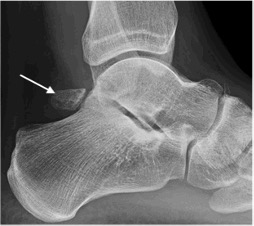

Posterior impingement with prominent os trigonum (arrow)